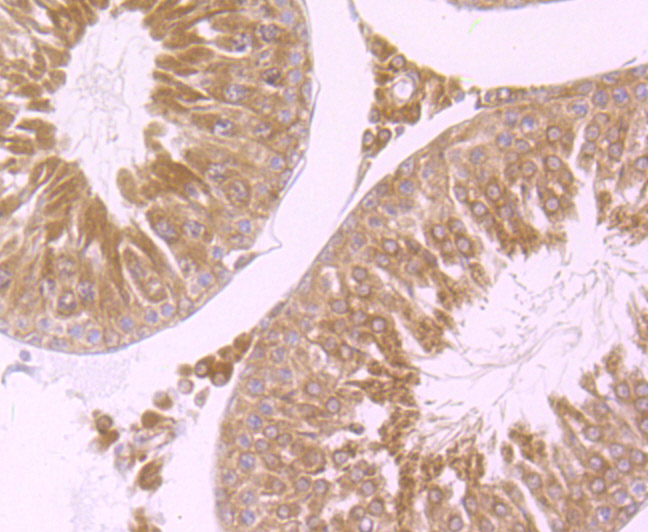

Paraformaldehyde-fixed, paraffin embedded (rat testis); Antigen retrieval by boiling in sodium citrate buffer (pH6.0) for 15min; Block endogenous peroxidase by 3% hydrogen peroxide for 20 minutes; Blocking buffer (normal goat serum) at 37°C for 30min; Antibody incubation with (Wnt2b) Monoclonal Antibody, Unconjugated (bsm-54266R) at 1:50 overnight at 4°C, followed by operating according to SP Kit(Rabbit) (sp-0023) instructionsand DAB staining.